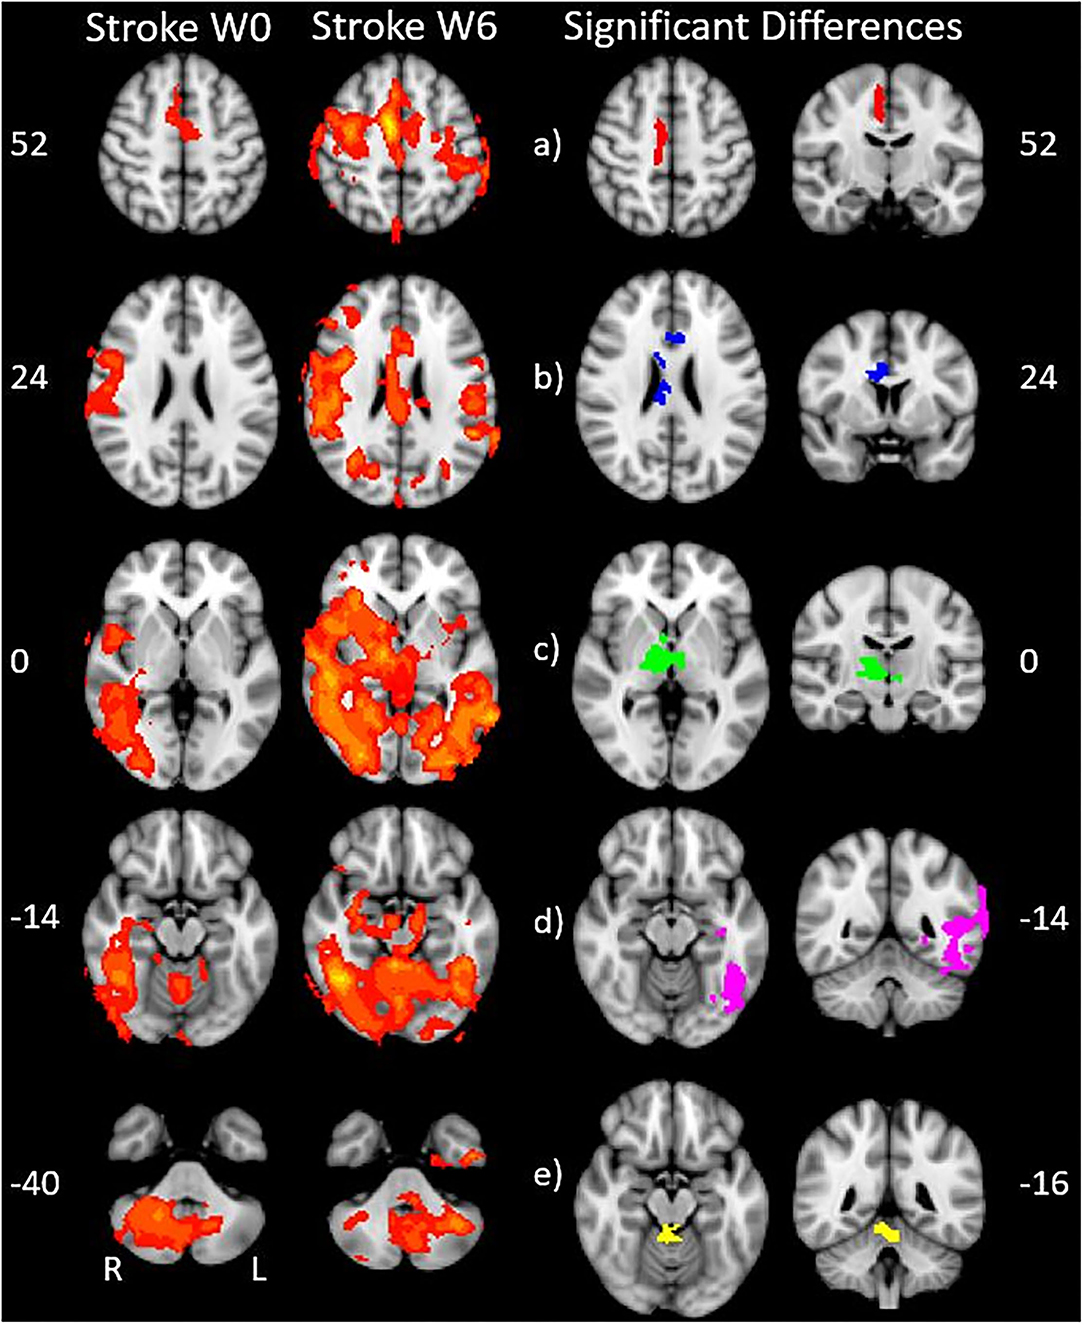

We found expected activity patterns and no significant difference between W0 and W6 sessions for controls. Across sessions, controls consistently and significantly activated bilateral primary motor (M1) and ipsilateral cerebellar areas at W0 and W6 (Figure 4) during right-hand movement. In addition to these regions, the ipsilateral premotor and supplementary motor area, bilateral hand portion of the M1, the thalamus and the putamen showed significant task-related activity. Although control participant's activity maps were similar across sessions, stroke participants showed differences between W0 and W6 (Figure 5). At W6 there was more widespread and bilateral activation in the stroke group compared with W0; whereas activation before injection was restricted to the contralesional hemisphere, activation increased in both hemispheres after injection (Figure 5). Activation maps yielded p-values for each voxel; these maps were threshold with p < 0.05 to assess significance. Significant differences (p < 0.05, df = 8; z > 2.3; paired z-test) between W6 and W0 in the stroke group included: (1) contralesional premotor cortex (PMC-R), (2) contralesional cingulate gyrus (CG-R), (3) contralesional thalamus (Th-R), (4) somatosensory and visual integration areas (Sens-IA), and (5) superior cerebellum (S-CB). These regions of activation are further described in Table 4 and illustrated in Figure 5.

Figure 5. Stroke differences during BoNT-A injections. The first two columns show significant (p < 0.05) levels of activity across the stroke group for W0 (left) and W6 (right). Columns 3 and 4 show the coronal (left) and axial (right) view of significant increase in activity following the BoNT-A intervention, displayed as five regions of interests. These areas are: (a) right premotor cortex (b) right cingulate gyrus (c) right thalamus (d) sensory integration area, (e) superior cerebellum. The physical coordinates of the axial slices are shown to the left or right of axial images, and the coronal views are denoted by the yellow horizontal lines.

The five identified regions of activation were subsequently used as masks to identify the number of active voxels in the given volume for the stroke group at W0 and W6 (Figure 6). Participants with stroke showed a significantly increased number of active voxels in all five regions following BoNT-A injections.